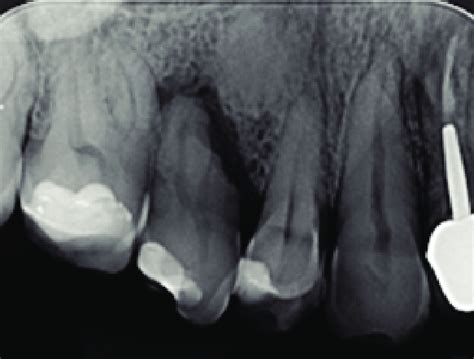

El quiste radicular se diagnostica mediante radiografías periapicales, en la radiografía los quistes se observan como una lesión radiolúcida (negras) con los bordes bien delimitados por una delgada línea blanquecina, de forma redondeada u ovalada. Sin embargo, la confirmación de la presencia de un quiste radicular se obtiene mediante imágenes radiográficas como las radiografías periapicales, las ortopantomografías (visión panorámica de ambos maxilares) o las tomografías computarizada de haz cónico (CBCT).